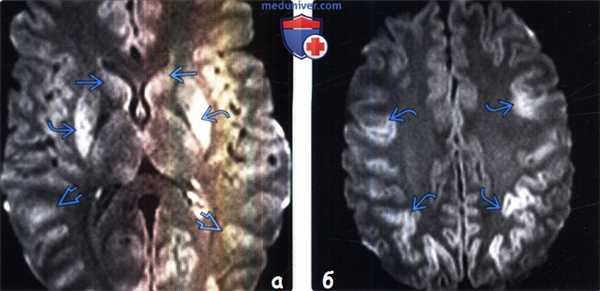

(а) У мужчины 57 лет после курения героина методом «погони за драконом» остро развилась лейкоэнцефалопатия. По данным МРТ определяется диффузное повышение интенсивности сигнала на T2-BИ/FLAIR-изображении (слева), и острое ограничение диффузии (справа).

(б) По данным МРТ у женщины 32 лет с передозировкой метадоном отмечается симметричное повышение интенсивности сигнала на T2-BИ/FIAIR-изображении в сочетании с острым ограничением диффузии на ДВИ.